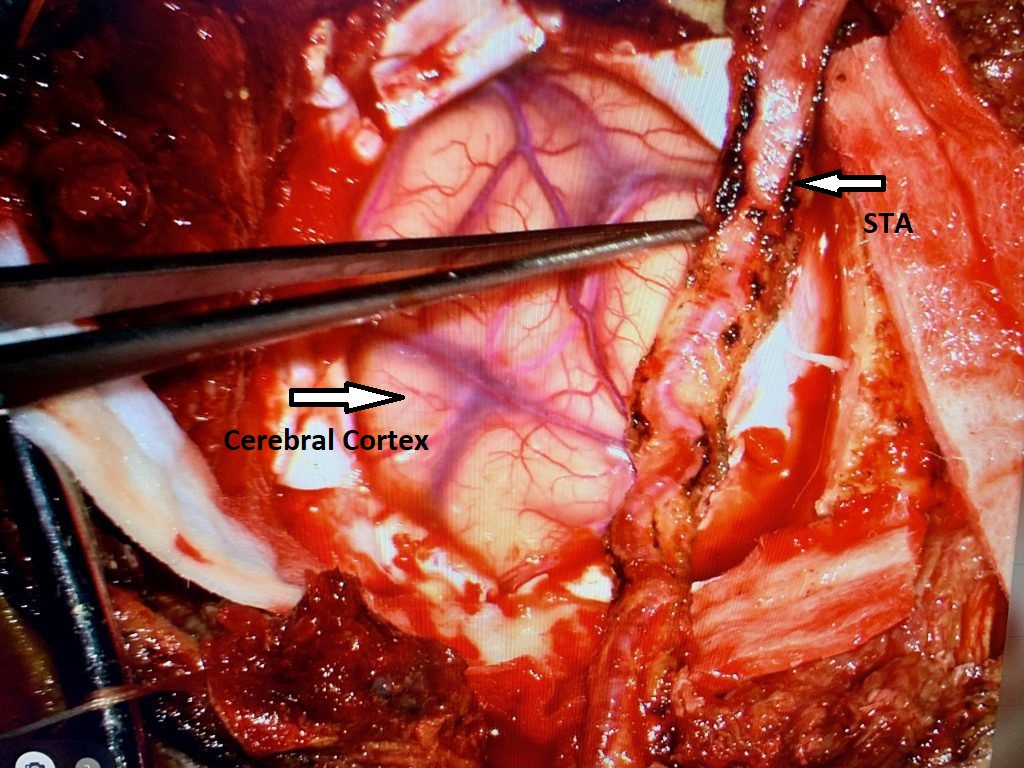

Brain:

Neurosurgeons Collaborate to Treat Giant Symptomatic Meningioma

Author: Ramin Rak M.D., F.A.A.N.S., F.C.N.S., Jonathan L. Brisman M.D., F.A.C.S., Read More!